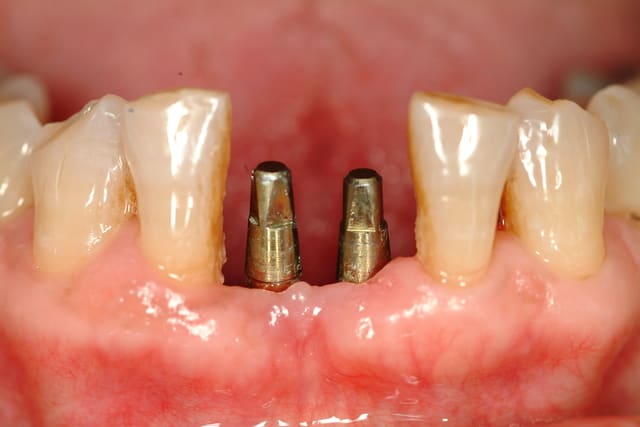

> Cas clinique:

> Edentements de 31 et 41

> Largeur mésio distale : 1.1 cm

> Volume osseux résiduel satisfaisant.

> Occlusion favorable.

A ta place je poserai deux implants Monobloc.

Même les implants de 3.3 mm en deux pièces sont plus volumineux que ces implants Monobloc.

Avantage: ils font 2.9 mm de diam au col et te permettent de garder suffisament d'espace entre les implants et les denst adjacentes.

Inconvénient: comme ils sont Monobloc, le placement doit être idéal, peu de retouches possibles et faire de la mise en temporisation immédiate.

c'est une très bonne solution, d'autant qu'étant monoblocs, il n'existe pas de microgap entre le moignon et l'implant. Ainsi, comme le souligne marcB6, les distances inter-implants et implants-dents peuvent être minimisée: utilisables même en cas d'un espace de 8.7 mm

Bravo, tu as raison, ceux sont des ARRP de chez Alpha bio.

tu doit enfouir la partie sablée de l'implant, elle est grise, le col doré est transmuqueux.

tu peux aussi l'enfouir mais dans ce cas, tu induis une cratérisation et un déplacement apical de ta crête osseuse.

Tu peux effectivement retoucher la partie occlusale, dans une certaine limite, car le moignon est déjà assez fin.

Evdemment, dans ce cas, extraction-implantation et mise en temporisation immédiate.